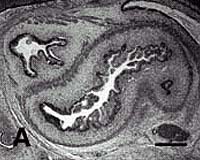

After several weeks, Mao and his colleagues found that the tissue-engineered structures retained the molded shape of the human mandibular condyle, with bone-like tissue underneath and a layer of cartilage-like tissue on top -- an arrangement similar to that of a natural articular condyle.

Moreover, multiple tests confirmed that the newly grown tissues were indeed bone and cartilage, having the characteristic microscopic components: for bone, a matrix of collagen with deposits of calcium salts, and for cartilage, collagen and large amounts of substances called proteoglycans.